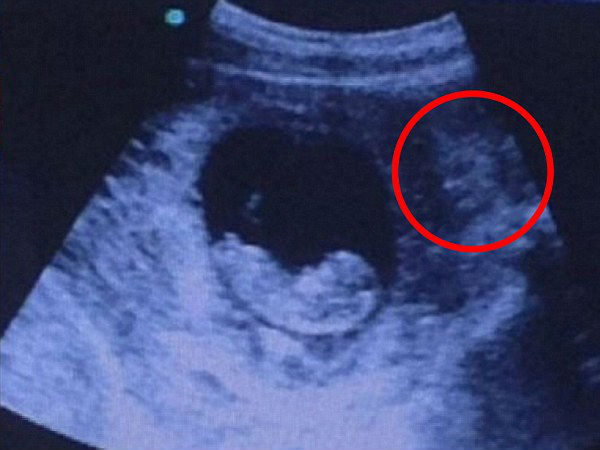

அப்படியான. ஒரு அல்ட்ராசவுண்ட் மருத்துவ பரிசோதனையின் போது கிடைத்த புகைப்படம் ஒன்றுதான் தற்போதைய 'திகிலான' இன்டர்நெட் வைரல் ஆகும்..!

இம்ஜர் (Imgr) எனப்படும் அடையாளம் தெரியாத நபரால் ஆன்லைனில் பதிவு செய்யப்பட்ட இந்த அல்ட்ராசவுண்ட் புகைப்படம் ஆனது இரண்டே நாட்களில் சுமார் மில்லியன் முறை பார்க்கப்பட்டுள்ளது.

இந்த வைரல் புகைப்படத்தில் கருவில் இருக்கும் சிசுவை 'டிமோன்' (Demon) ஒன்று, அதாவது அரக்க வடிவம் கொண்ட ஒருவன் அல்லது துர்தேவதை ஒன்று அருகில் இருந்தப்படியே கண்காணிப்பது போன்று பதிவாகியுள்ளது.

எட்டு முதல் பத்து வாரம் நிரம்பிய இந்த கருவின் வெளிப்புறத்தில் நிர்வாண உடலோடு ஒரு உருவம் நிற்பதை தெளிவாக காண முடிகிறது.

மேலும் இந்த புகைப்படத்தை பதிவு செய்தவர் "தோழி ஒருவரின் அல்ட்ராசவுண்ட் புகைப்படம், இதை நீங்கள் காணும் போது" என்று எழுதி, புத்தாண்டு அன்று பதிவு செய்துள்ளார்.

இந்த புகைப்படத்தை நான்கு ஆராய்ந்தால் சிசுவின் அருகே நிற்கும் இந்த உருவத்திற்கு இரண்டு கருமையான கண்கள் மற்றும் தலையில் கொம்பு போன்ற வடிவம் இருப்பதையும் காண முடிகிறது.

இதை ஒரு துர்தேவதையாக மட்டும் பார்க்க கூடாது, இந்த உருவம் பார்க்க ஹாலிவுட் திரைப்பட கதாப்பாத்திரமான வொன்டர்வுமன் போலவும் தோன்றுகிறது என்பதும் நிதர்சனம் தான் !

ஆனால் இந்த போட்டோ சார்பாக அல்ட்ராசவுண்ட் தொழில்நுட்ப வல்லுநர்களிடம் இருந்து எந்த விதமான விளக்கமும் கிடைக்கப்பெற வில்லை என்பதும் குறிப்பிடத்தக்கது.